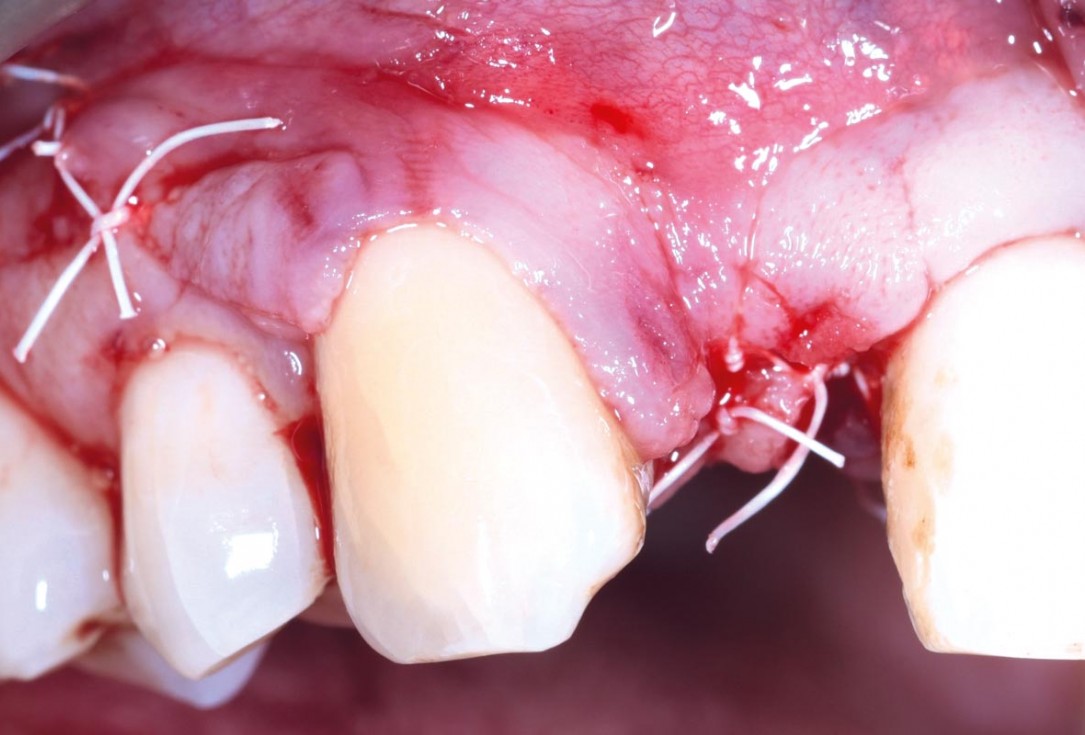

05/13 - Full muco-periostal flap elevation

09/13 - Closure with PTFE sutures